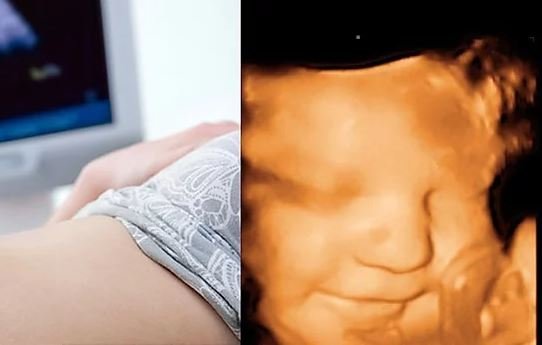

O ultrassom é um exame de imagem realizado por um transdutor, aquele aparelhinho que o médico encosta na pele da pessoa e que emite e capta ondas sonoras por meio do contato com o corpo humano. Com base nessa avaliação, imagens são formadas e investigadas por um médico.

Durante o exame, que dura cerca de 30 minutos (o tempo varia conforme a aplicação), o dispositivo “troca sons” com o corpo. Como assim? Ora, as ondas sonoras entram e os ecos de sua passagem pelo corpo são “escutados” pelo computador, que transforma os sinais em fotos ou vídeos.

A partir dessa avaliação, imagens em 2D e em 3D são geradas e, então, interpretadas pelo radiologista, que emite laudos sobre a composição da parte do corpo investigada. Em tons de cinza, podem aparecer massas, lesões ou presença de líquidos, assim como alterações na estrutura, altura e composição de órgãos e tecidos moles.